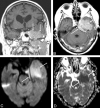

CNS lymphoma consists of 2 major subtypes: secondary CNS involvement by systemic lymphoma and PCNSL. Contrast-enhanced MR imaging is the method of choice for detecting CNS lymphoma. In leptomeningeal CNS lymphoma, representing two-thirds of secondary CNS lymphomas, imaging typically shows leptomeningeal, subependymal, dural, or cranial nerve enhancement. Single or multiple periventricular and/or superficial contrast-enhancing lesions are characteristic of parenchymal CNS lymphoma, representing one-third of secondary CNS lymphomas and almost 100% of PCNSLs. New CT and MR imaging techniques and metabolic imaging have demonstrated characteristic findings in CNS lymphoma, aiding in its differentiation from other CNS lesions. Advanced imaging techniques may, in the future, substantially improve the diagnostic accuracy of imaging, ultimately facilitating a noninvasive method of diagnosis. Furthermore, these imaging techniques may play a pivotal role in planning targeted therapies, prognostication, and monitoring treatment response.